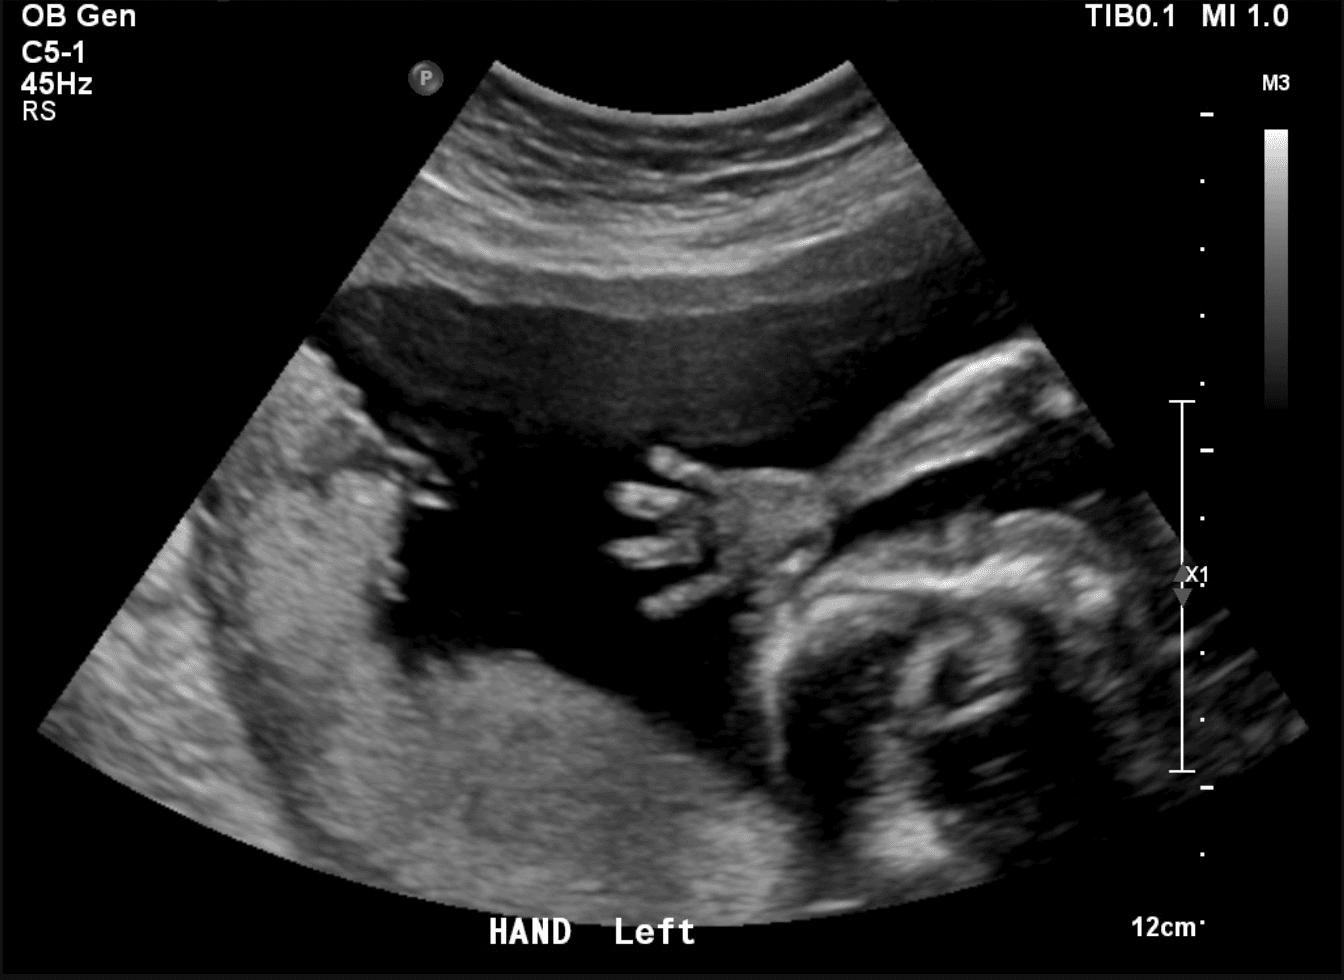

This scan shows a baby at 22 weeks gestation captured during a Well Baby Scan at Ultrasound Ireland.

At 22 weeks, your baby is about the size of a papaya and weighs around 430g. You can see:

- Detailed facial features

- Fingers and toes

- Baby practising breathing movements

- Lots of active movement - kicks, stretches, and rolls